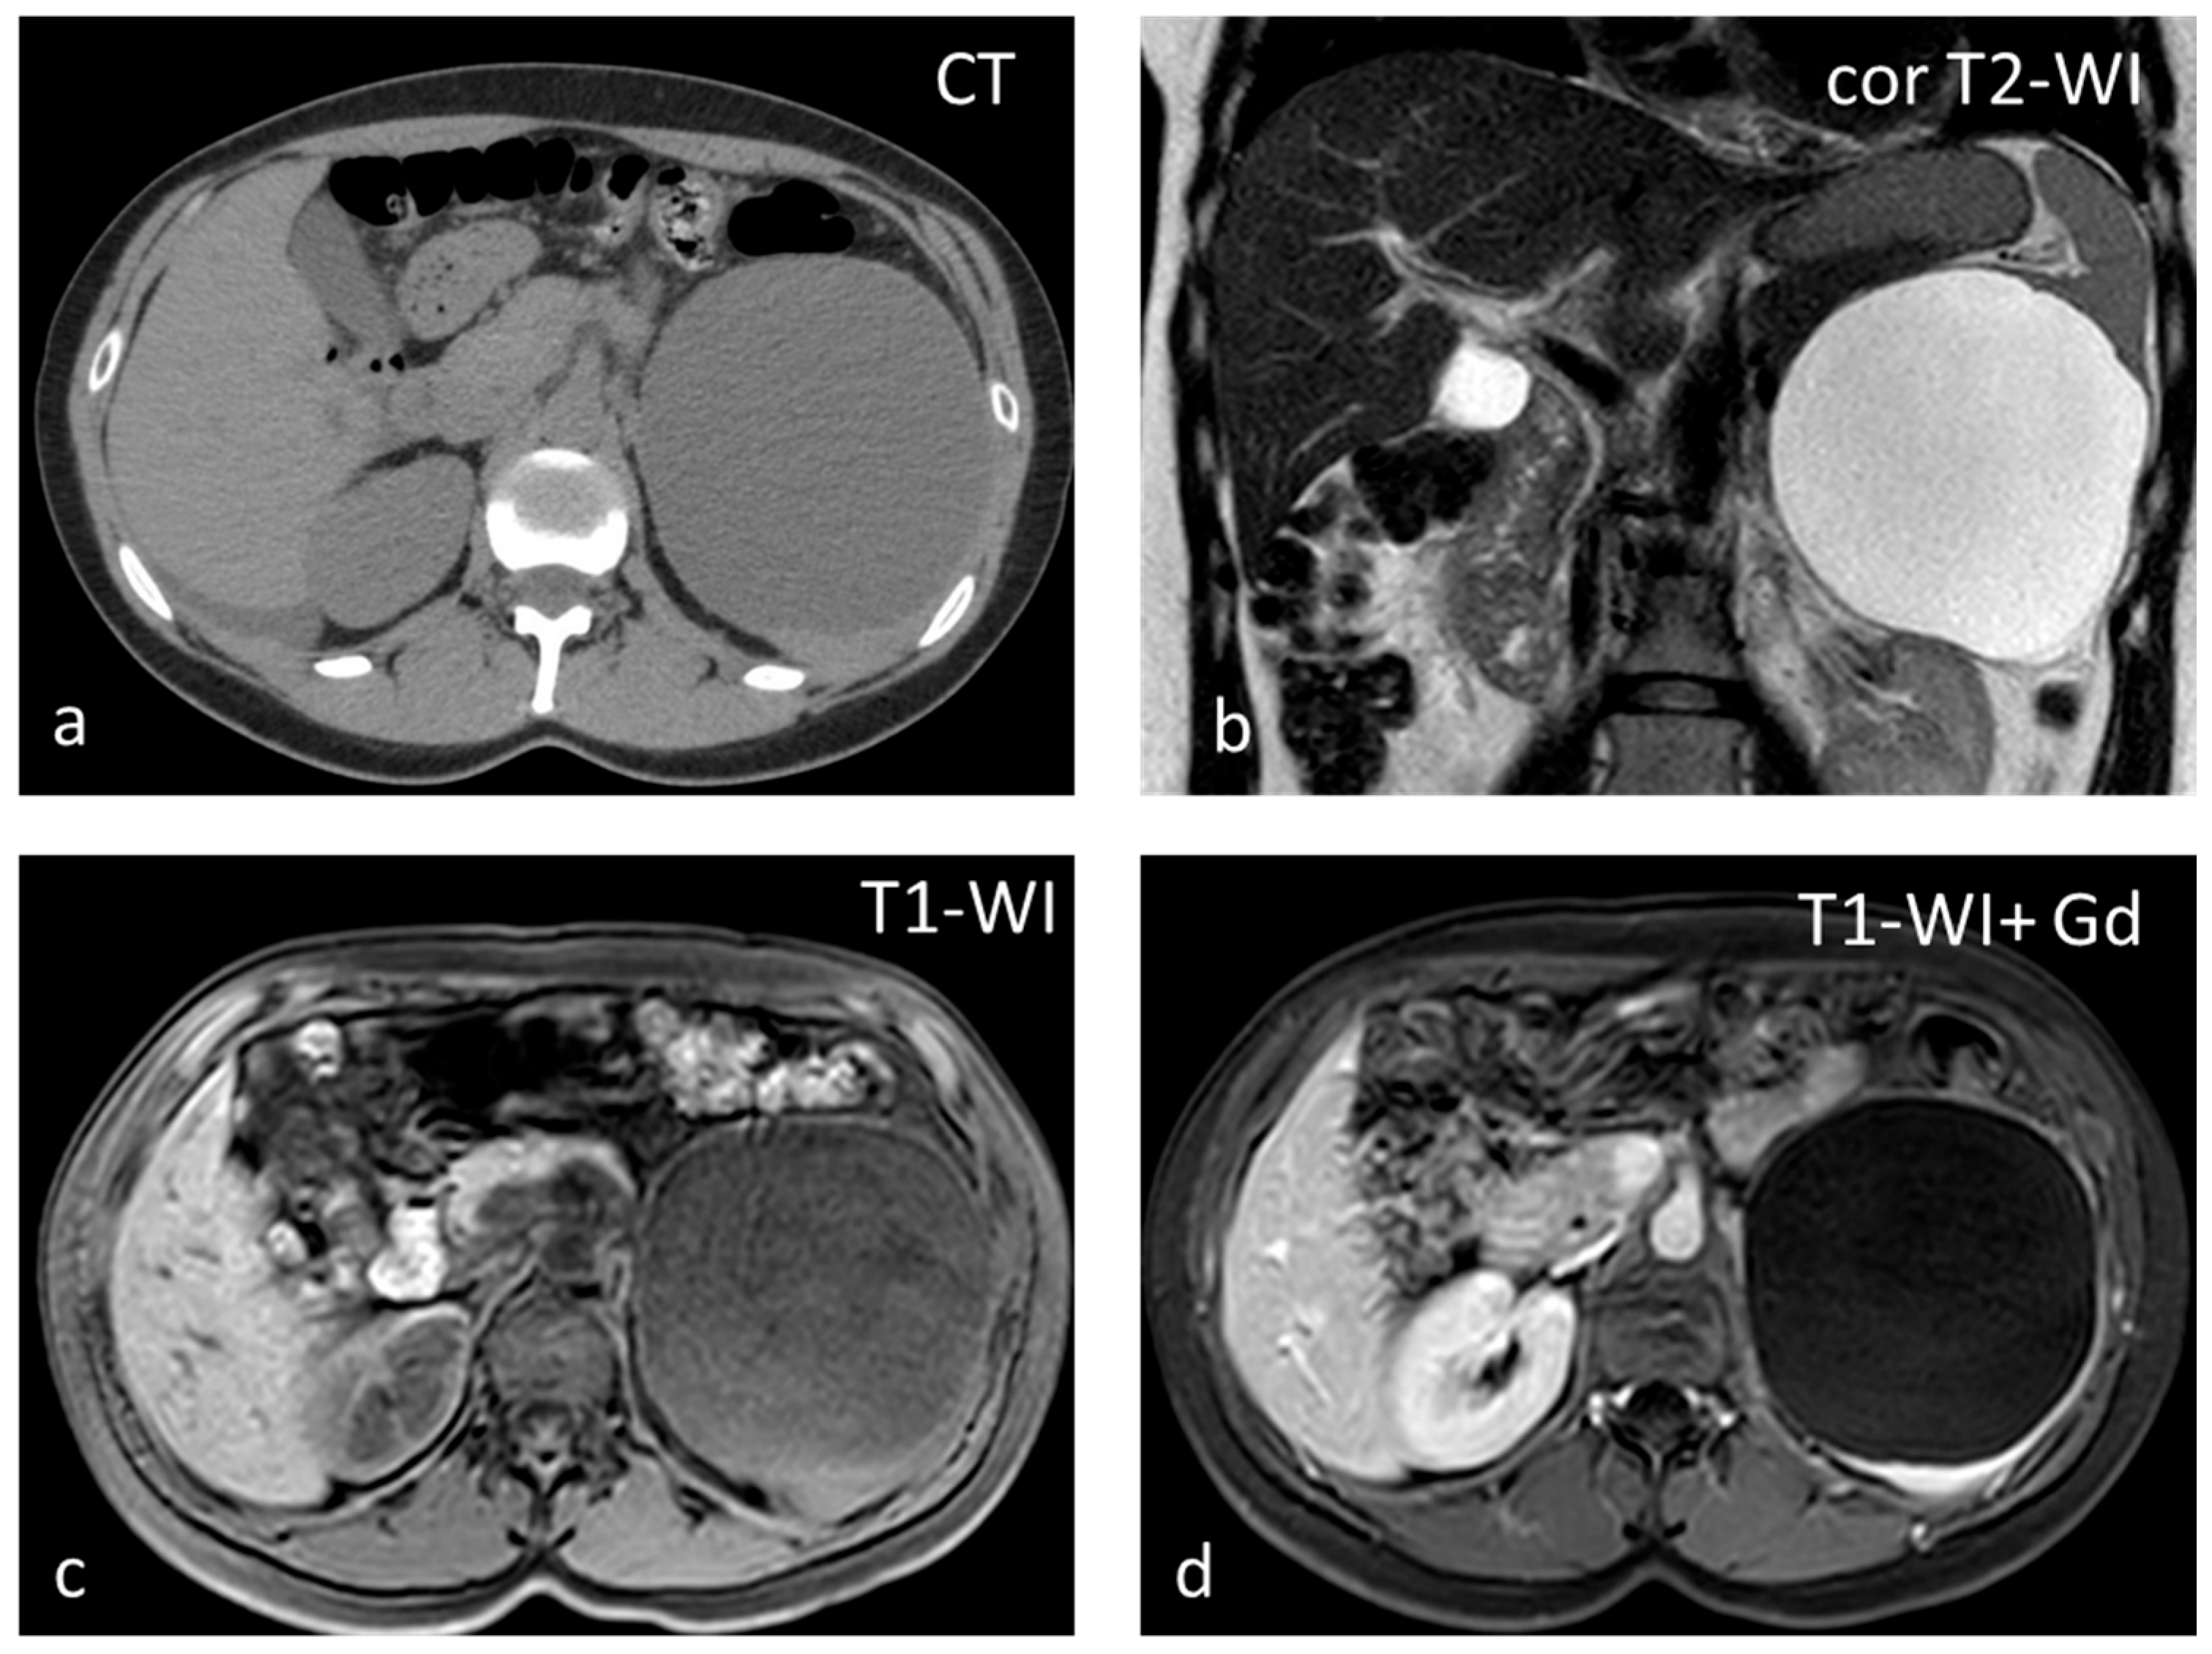

Sclerosing Angiomatoid Nodular Transformation (SANT) is a rare benign vascular disorder of unknown cause, with the same prevalence as inflammatory pseudotumors and approximately 170 cases described in the scientific literature. SANT is almost exclusively described in the spleen, except for one reported in the adrenal gland [41]. Half of SANTs are asymptomatic, and half are diagnosed because of abdominal pain, pancytopenia, and splenomegaly. SANT is considered a disease of slight female preponderance. The patients usually present in the 30- to 60-year age group. Splenectomy is a useful and effective technique for the management of SANT. SANT patients have a good prognosis, with no recurrence after splenectomy [42]. SANT is formed by multiple coalescing angiomatoid nodules from the red pulp embedded within a dense fibrous stroma [42]. The nodules are constituted by irregular vascular spaces lined by thick endothelial cells; the fibrous bands coalesce to form a central stellate fibrous scar. SANT appears as a well-circumscribed, solitary round mass, typically 3–17 cm in size. It is often mistaken for a sclerosed hemangioma or an inflammatory pseudotumor and can mimic a malignancy [41]. On CT, they present as iso- to hypoattenuating masses, while they appear isointense on T1-WI but can show areas of hyperintensity or susceptibility if a hemorrhage is present. T2-WI shows a heterogeneous, predominantly hypointense mass with hyperintense septa radiating toward the center (Figure 7). Contrast enhancement may be peripheral with radiating lines (spoke-wheel pattern), rim-like, and progressive. In the delayed phase, SANTs appear homogeneous. Moderate and heterogeneous 18F-FDG avidity has also been reported [43].

Figure 7.

SANT appearing slightly hypodense on non-contrast CT (a) and isointense on T1-WI (b), with small areas of hyperintensity due to hemorrhage. On T2-WI (c), the lesion is heterogeneous, predominantly hypointense, with hyperintense radiating septa. After gadolinium administration, enhancement is progressive (c–f) along the radiating septa converging toward the center of the lesion.